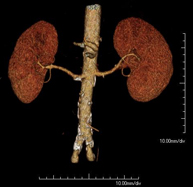

Prova diagnòstica no invasiva que consisteix en l'estudi de l'artèria aorta abdominal a través de l'obtenció d'imatges d'alta definició anatòmica mitjançant l'ús d'un equip de TC (Tomografia Computeritzada) i de contrast iodat. La qualitat de les imatges permet realitzar reconstruccions en 2D i 3D gràcies a estacions de treball especialitzades en l'estudi arterial. Està indicat en aquells pacients amb malaltia vascular (arteriosclerosi), en aneurismes d'aorta, en pacients amb dolor abdominal de possible origen vascular, en estudis prequirúrgics de lesions adjacents a l'aorta abdominal com a "mapa" vascular. La informació obtinguda de manera no invasiva és indispensable per als pacients que requereixen tractament percutani o quirúrgic. En aquells pacients que només requereixen seguiment de les lesions vasculars, aquesta tècnica és la tècnica no invasiva d'elecció juntament amb l'angio-RM. - Angio-TC Artèries renals

Prova diagnòstica no invasiva que consisteix en l'estudi de les artèries renals a través de l'obtenció d'imatges d'alta definició anatòmica mitjançant l'ús d'un equip de TC (Tomografia Computeritzada) i de contrast iodat. La qualitat de les imatges permet realitzar reconstruccions en 2D i 3D gràcies a estacions de treball especialitzades en l'estudi arterial. Està indicat en aquells pacients amb malaltia vascular (arteriosclerosi), en aneurismes d'aorta, en pacients amb dolor abdominal de possible origen vascular, en estudis prequirúrgics de lesions adjacents a l'aorta abdominal com a "mapa" vascular. La informació obtinguda de manera no invasiva és indispensable per als pacients que requereixen tractament percutani o quirúrgic. En aquells pacients que només requereixen seguiment de les lesions vasculars, aquesta tècnica és la tècnica no invasiva d'elecció juntament amb l'angio-RM. - Angio-TC Aorto-ilíac

Prova diagnòstica no invasiva que consisteix en l'estudi de l'artèria aorta abdominal amb l'obtenció d'imatges d'alta definició anatòmica mitjançant l'ús d'un equip de TC (Tomografia Computaritzada) i contrast iodat. La qualitat de les imatges permet realitzar reconstruccions en 2D i 3D gràcies a estacions de treball especialitzades en l'estudi arterial. Està indicat en aquells pacients que pateixen malaltia vascular (arteriosclerosi), aneurismes d'aorta, en pacient amb dolor abdominal d'un possible origen vascular, en estudis prequirúrgics de lesions adjacents a l'aorta abdominal com el "mapa" vascular, etc. La informació obtinguda de forma no invasiva és indispensable per als pacients que requereixen tractament percutani o quirúrgic. En aquells pacients que només requereixen un seguiment de les lesions vasculars, aquesta tècnica és la tècnica no invasiva d'elecció juntament amb l'angio RM. - Angio TC d'artèries renals

Prova diagnòstica no invasiva que consisteix en l'estudi de les artèries renals amb l'obtenció d'imatges d'alta definició anatòmica mitjançant l'ús d'un equip de TC (Tomografia Computaritzada) i contrast iodat. La qualitat de les imatges permet realitzar reconstruccions en 2D i 3D gràcies a estacions de treball especialitzades en l'estudi arterial. Aquesta prova està indicat en aquells pacients que pateixen HTA refractària al tractament, en pacients amb lesions renals que tenen un mapa vascular prequirúrgic, etc. - Angio TC d'aorta-ilíaca